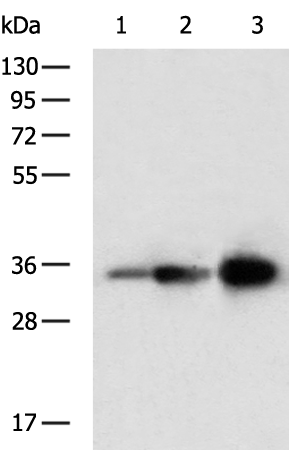

分类: 科研抗体货号: P08401别名: HL应用: WB,IHC反应种属: Human, Mouse, Rat